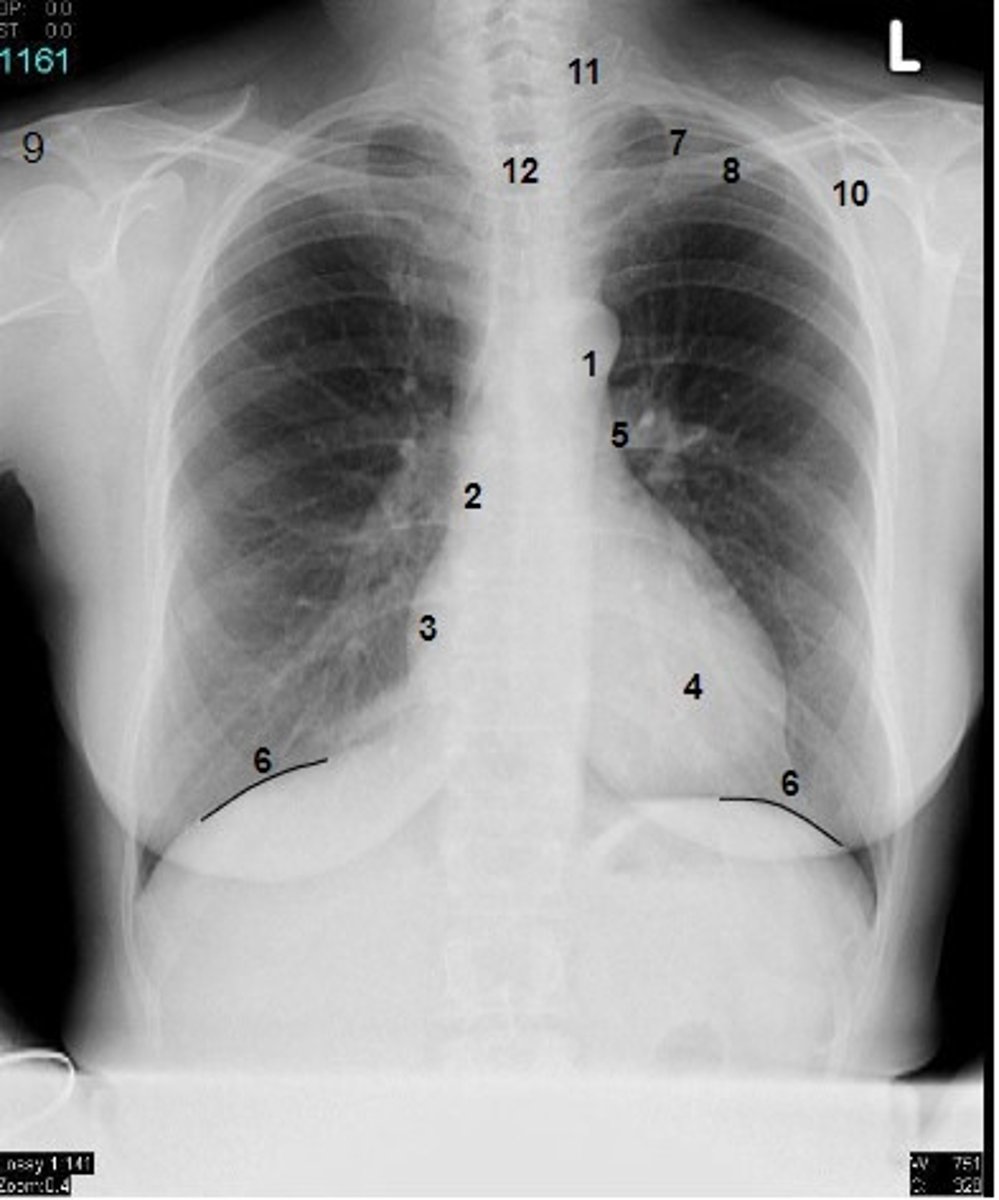

1

at what number is the arch of aorta?

2

at what number is the superior vena cava

3

at what number is the right atrium

4

at what number is the left ventricle

5

at what number is the primary bronchus

6

at what number is the dome of diaphragm

7

at what number is the first rib

8

at what number is the clavicle

9

at what number is the acromion of scapula

10

at what number is the coracoid process of scapula

11

at what number is the transverse process of vertebra

12

at what number is the spinous process of vertebra